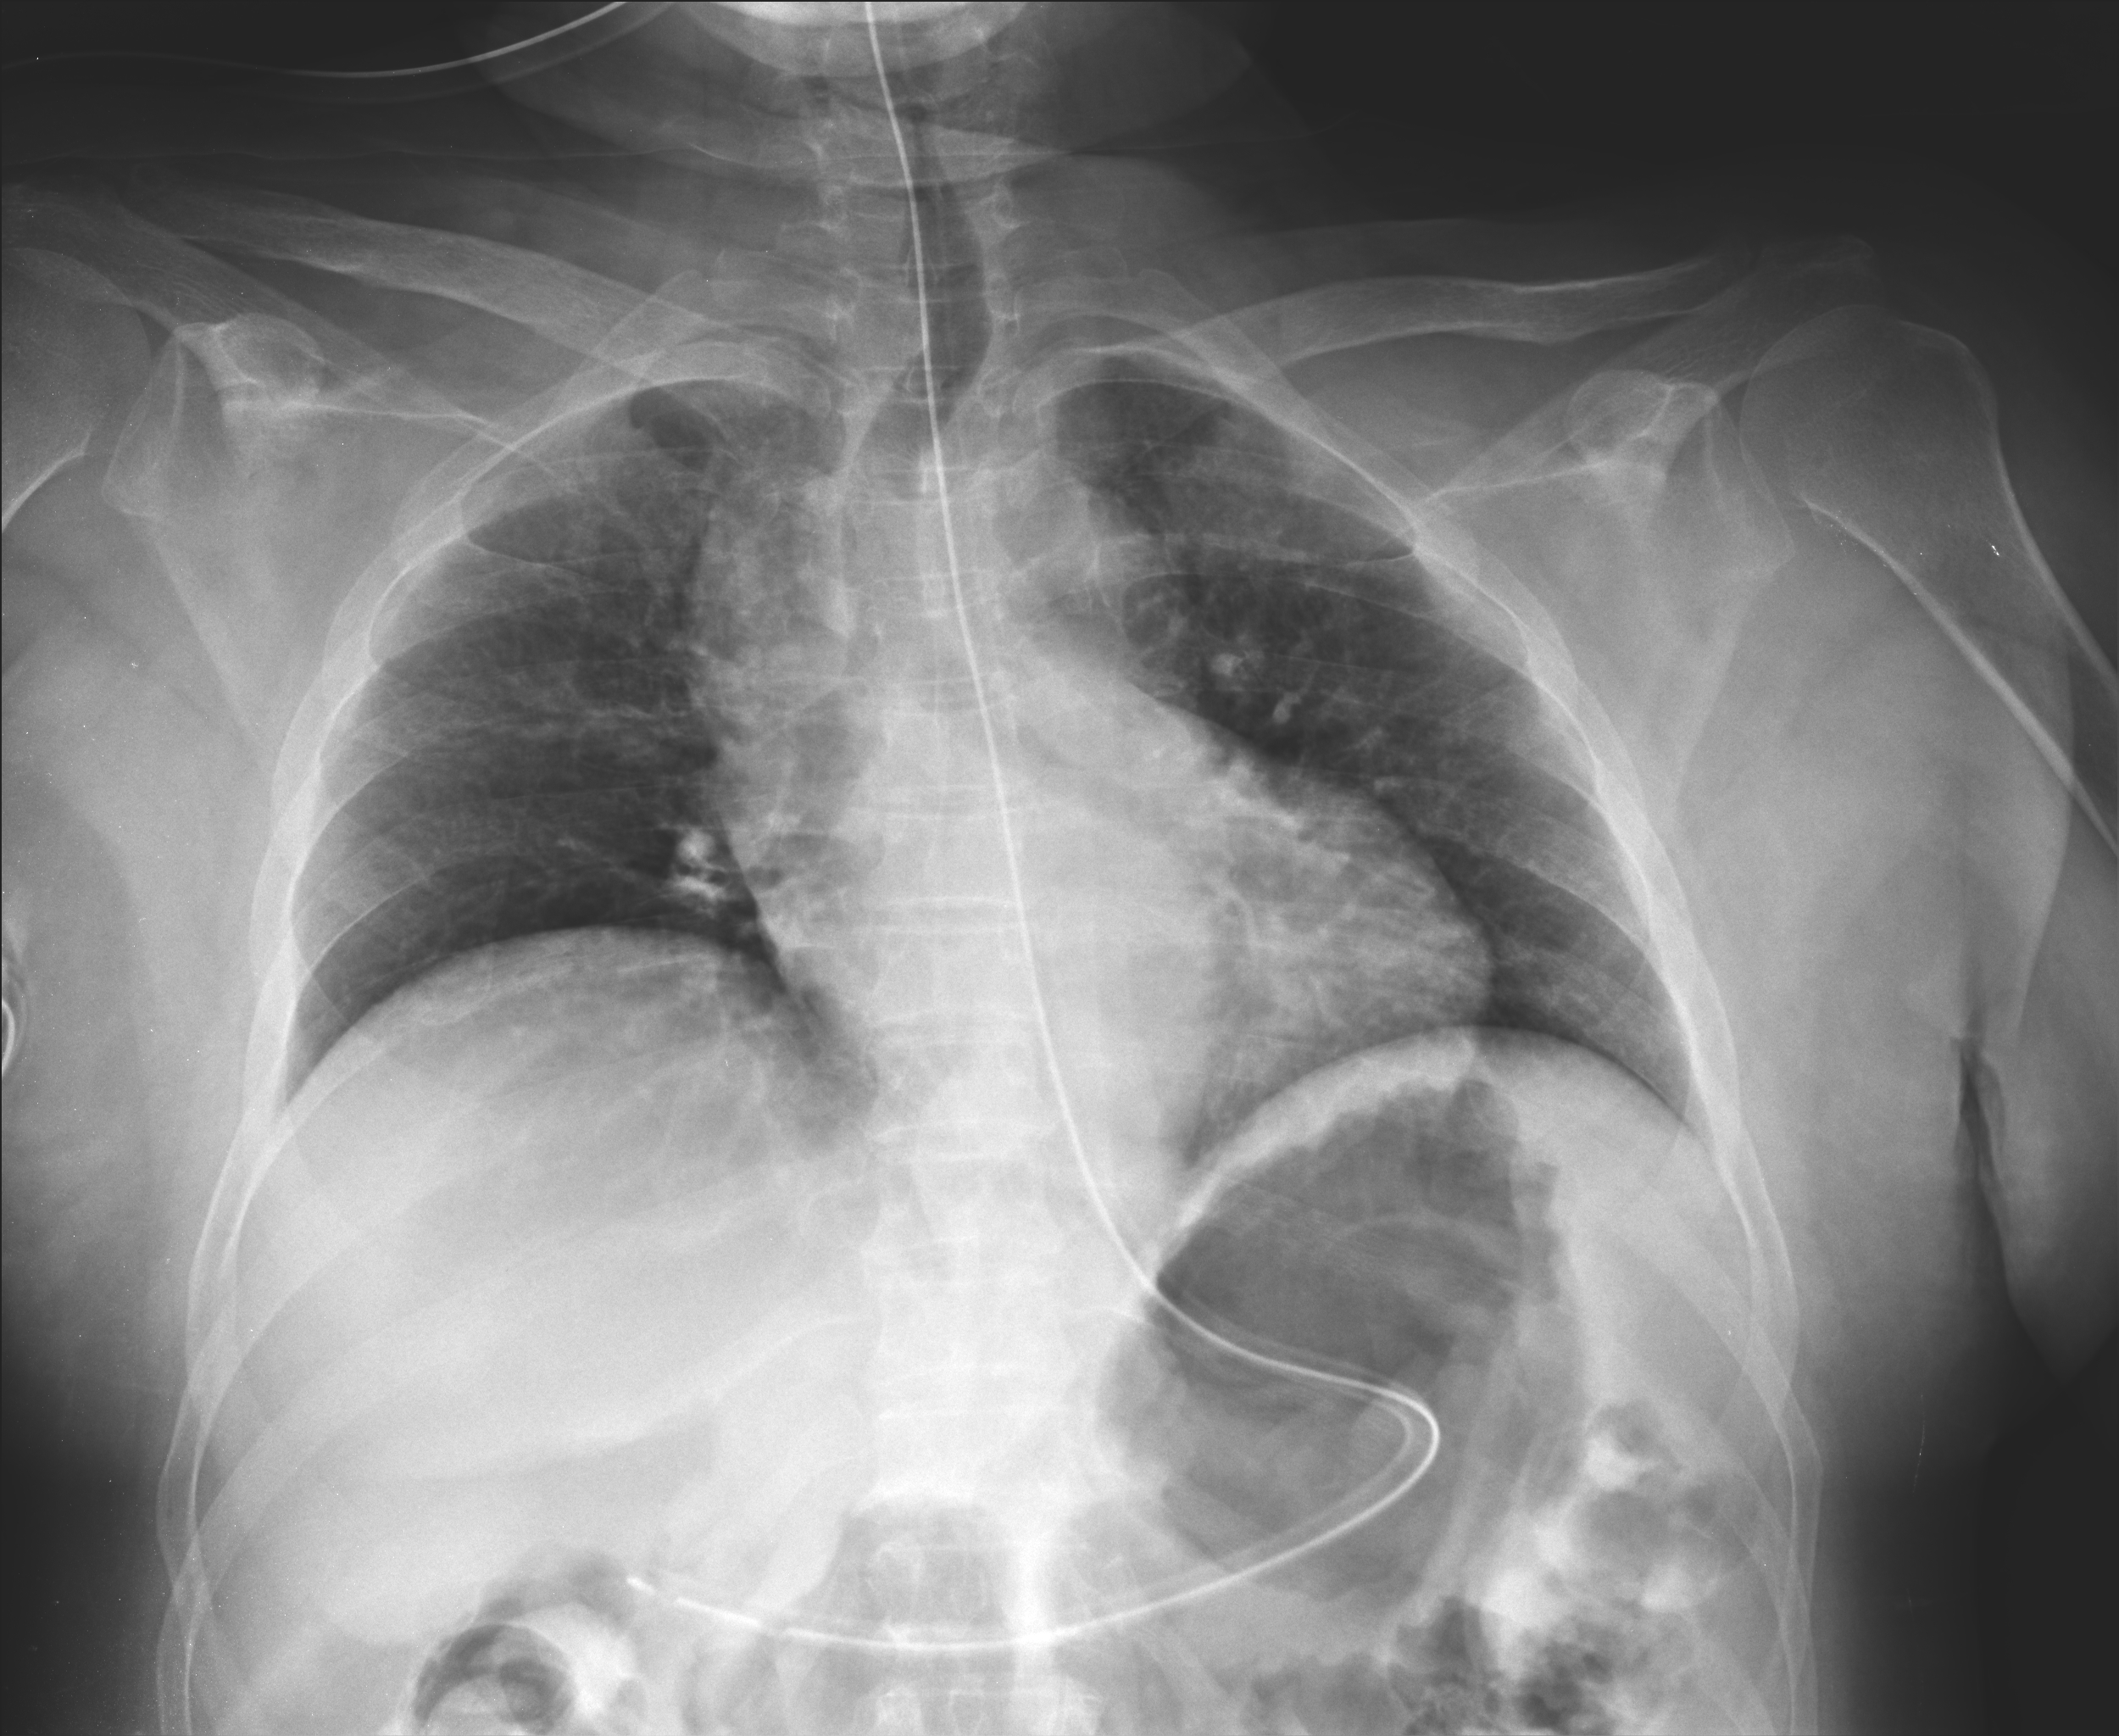

Pneumoperitoneum (PP) in peritoneal dialysis (PD) patients is a rare complication; however it should be considered to avoid an unnecessary laparotomy and that will also compromise the dialytic options. A 70 year-old woman with end-stage renal disease had been on chronic PD with automated night therapy for 21 months, without complications or any signs of peritonitis. She was admitted with a sudden epigastric pain. Tympanic abdomen was present on physical examination. The Tenckhoff catheter exit site looked unremarkable. Laboratory testing showed a normal white cell count. An important PP was visible in chest and abdominal X-rays. Contrast-enhanced abdominal CT scan confirmed a generalised PP distributed in supramesocolic recesses. No extravasation of endoluminal contrast was seen. Dialysis catheter was placed at left lower quadrant. We performed the aspiration of PP using an aseptic technique in Trendelenburg position. Abdominal X-ray showed resolution of PP. In the following day she was asymptomatic but abdominal X-ray revealed a newly developed PP, thus we decided to remove the catheter with no recurrence of PP.Downloads